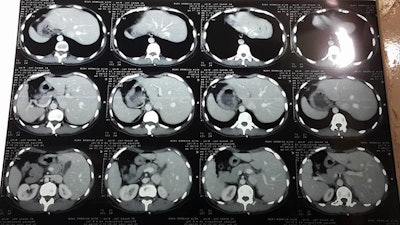

Screenshot of a Facebook post that includes a link to the patient's CT scan images. Discussion between the radiologist and the clinical team took place in a form of Facebook comments. All images courtesy of Dr. Abdulrahman Masrani.Between February 2015 and January 2018, 497 radiology exams were interpreted by TRG, including 374 CT scans (75%), 119 plain films (24%), and four ultrasound scans (1%). Most CT exams (97%) were performed without contrast, due to the shortage and prohibitive cost of contrast media.

The biggest challenge for TRG radiologists has been reading CT studies performed without contrast, particularly in trauma cases, according to Masrani and colleagues. Even the few contrast-enhanced CT scans are of low diagnostic value due to poor-quality scanners, improper timing of intravenous administration, and poor protocol and acquisition parameters.

"In some instances, submitted images were taken by cell phone camera capturing poorly projected radiographic films or printed CT images on viewing boxes," they wrote.

Printed CT images were accidentally placed in reverse on the viewbox and captured by a cellphone camera and sent to the TRG for interpretation.Despite these obstacles, the project has continued and seems to be helping, Masrani and colleagues noted.